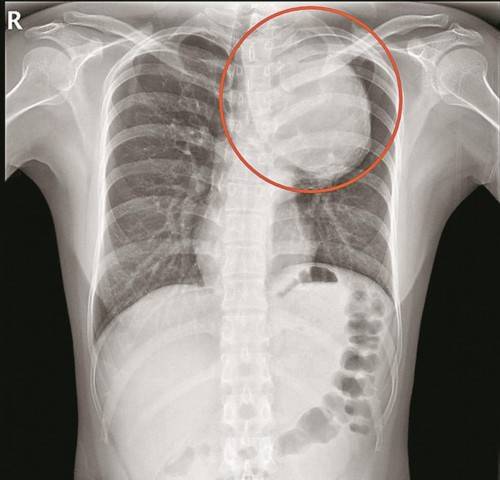

▲胸片显示动脉瘤很大

“患者的胸主动脉瘤非常大 , 位于主动脉弓降部 , 它会像吹气球一样 , 越长越大 。 正常人的主动脉弓部只有香肠那么大 , 而患者的主动脉瘤直径达75mm , 已经有青芒那么大了 , 是正常人的5倍 , 瘤子像一条蟒蛇一样 , 从颈部长到膈肌 , 深入隐藏在患者体内 。 ”南方医科大学深圳医院心脏与血管外科主任杨建安说 。